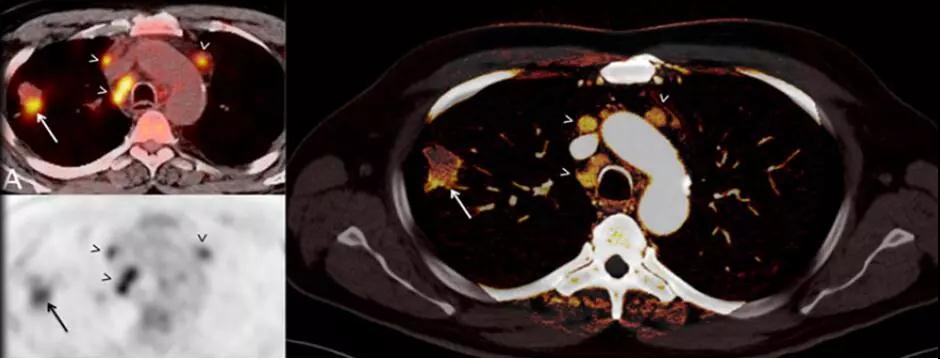

7. 類PET 成像:

傳統(tǒng)PET成像存在輻射劑量過高、放射污染、價格昂貴等局限性。

SOMATOMForce的純譜雙能量成像技術(shù)具有更好的靈敏度和特異性,使CT雙能量的應(yīng)用上升到一個前所未有的水平,應(yīng)用范圍更廣泛,不但可以常規(guī)對腫瘤組織類型、心血管疾病進(jìn)行更為精確的識別,更是突破影像界限,首次實現(xiàn)碘、鈣、水、脂肪、鐵等多物質(zhì)多元素多參數(shù)量化成像,能夠精準(zhǔn)評估骨髓挫傷水腫、腫瘤浸潤活性。

△提高診斷準(zhǔn)確性-肺結(jié)節(jié)能量碘圖